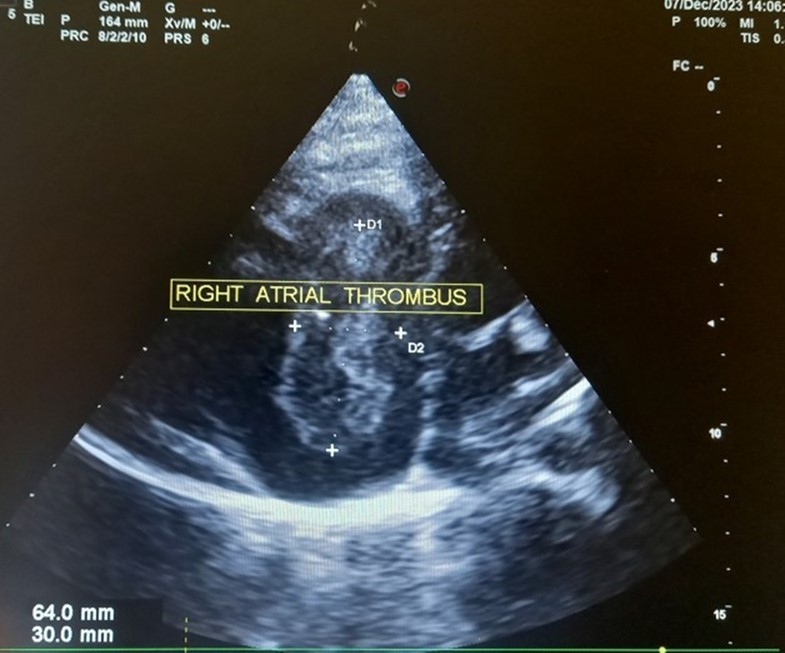

The patient underwent echocardiography (Figure 3 ) showing a low insertion of the septal and posterior leaflets of the tricuspid valve 22 mm below the tricuspid annulus, the anterior leaflet having reduced reduced mobility. Significant dilatation of the the right atrium by atrialisation of the right ventricle (RV). The rudimentary RV and its atrial stump are dilated and responsible for compression of the LV. There was no tricuspid insufficiency. No other associated congenital anomaly. However, we found a large floating thrombus in the right atrium measuring 64 mm x 30 mm in diameter. This was therefore Ebstein's disease at stage C of the Carpentier classification. The apical displacement of the tricuspid septal valve was 22 mm or 15 mm/m2). The surface area of the atrium and the atrialized right ventricle was 45 cm2 , the surface area of the right ventricle and the left cavities was 30 cm2 , the Celermajer index was calculated at 1.4 ( Grade 3).

Figure 3.Transthoracic echocardiography, apical four chambers view . Apical displacement of the tricuspid valve (a) and right atrial thrombus (b).

The ECG abnormalitie found in our patient was atrial flutter. The patients with atrial flutter may be at an increased risk of a stroke compared with the general population because during atrial flutter blood may not move as rapidly through the upper heart chambers (the atria) as it does during normal sinus rhythm. Slower movement of the blood carries the risk of formation of small blood clots that can cause a stroke. The risk of stroke is not the same for all people with atrial flutter. Therefore, some people with atrial flutter may require treatment with a blood thinner called warfarin to reduce the risk of stroke 10

In our case, the patient had, type C of EA and Grade 2. The investigation also revealed a large thrombus floating in the right atrium and no obvious regurgitation of the tricuspid valve. In addition, the septa was intact, there was no persistence of the ductus arteriosus, the pulmonary and aortic pathway were unobstructed.

Our case highlights a rare form of Ebstein's disease with a large right intra-atrial thombus. It is a rare disease discovered late in adulthood with no vicarious shunt. Echocardiography is used to establish the diagnosis and to assess its severity. Ebstein's anomaly is tricuspid valve and right ventricular malformation with variability in anatomy, pathophysiology, and clinical presentation which cannot be managed surgically in our resource-limited setting. The great anatomical heterogeneity of EA generates a wide spectrum of clinical features at presentation which cannot be managed surgically in our context of limited resources. Hence the importance of antenatal ultrasound diagnosis with a view to possible termination of pregnancy.